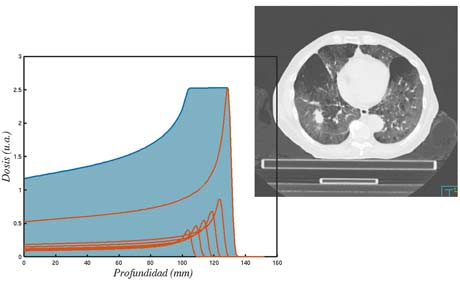

El cálculo de la dosis en los tratamientos de radioterapia externa es un desafío por la alta conformación de los haces de radiación en la tecnología actual (IMRT y VMAT). Estas técnicas adaptan los haces a la forma del tumor, de manera que la dosis recibida por los tejidos sanos es pequeña, pero el coste asociado es que cualquier error de posicionamiento o el movimiento del propio tumor (por ejemplo, por respiración) puede afectar a la dosis depositada.

Esta línea tiene por objeto utilizar herramientas de adquisicón de imagen (Cone Beam CT) y de procesado de imagen médica (registro deformable) para determinar la dosis real recibida por un paciente en cada sesión de tratamiento y así poder adaptar las sesiones restantes para alcanzar la dosis prescrita.

La dosis recibida por el tejido sano es de especial importancia cuando los pacientes son pediátricos o cuando se van acumulando tratamientos radioterápicos. Para este tipo de tratamientos está especialmente indicada la radioterapia con protones, disponible en la sede de Madrid de la Clínica Universidad de Navarra. En esta línea buscamos resolver los problemas asociados al Pencil-Beam Scanning y el movimiento interno del tumor.

En esta línea buscamos optimizar el procedimiento y la dosis en el caso de tumores pulmonares y oculares empleando desarrollos propios tanto de equipamiento como de herramientas computacionales